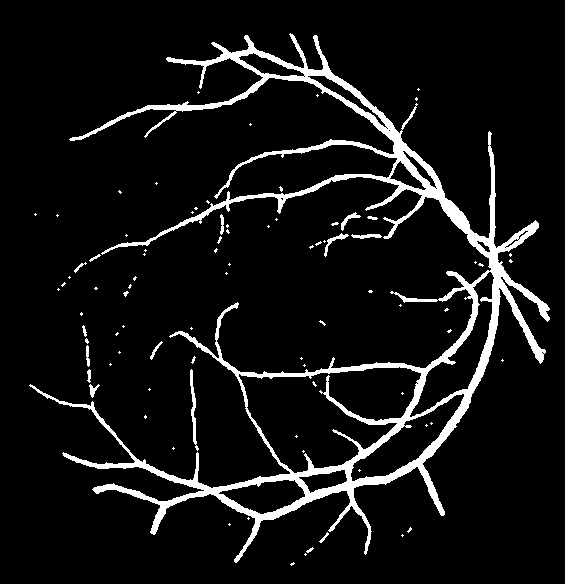

Figure 8: Visual results for two sample STARE images.

Cross Validation

Cross-validation is used to assess the performance of the proposed model on ten images from the STARE dataset. STARE images are more challenging due to the inherent lower quality and poor contrast of these images. However, the proposed model achieves reasonable performance on the STARE dataset images. Typically, training is conducted on STARE images using leave-one-out validation to test the model’s validity. Very few works have provided cross-validation to evaluate the stability of the learned model on the STARE dataset. The average values 88.06/96.31 for Se/Sp are quite promising and demonstrate the significant performance of the proposed model. The average AUC value is 97.57% that reflects the generalization of the proposed model on a completely unseen STARE dataset to demonstrate its generalization capability. Therefore, we, believe that our proposed methodology can be reliably applied for automatic retinal vessel segmentation of the clinical applications, such as a computer-aided diagnosis pipeline or automated vascular quantification or localization. Figure 8 depicts the visual outcomes for 2 sample images from the STARE dataset. As evident from a visual comparison of ground truth and output segmentation masks, thick vessels are detected quite accurately, especially near the fovea region. Similarly, thin vessel pixels at the branches are also segmented with reasonable visual match.